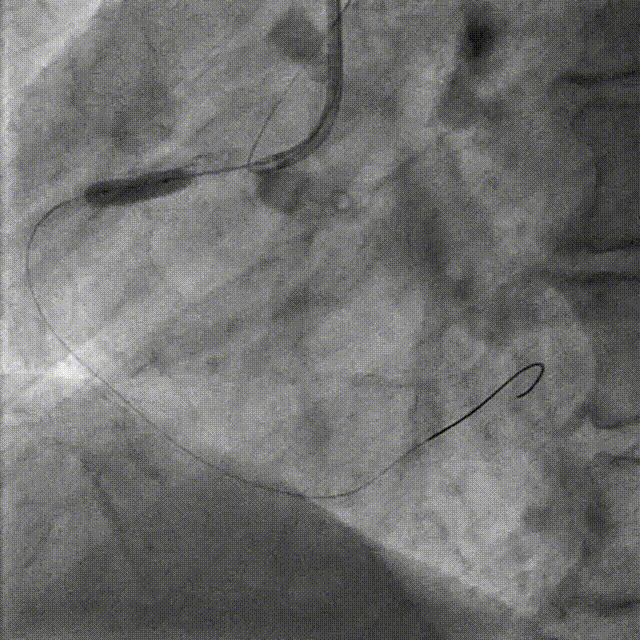

PCI-LAD TR, 7F EBU3.5

ROTA with 2.0mm burr

Angiography & Angioplasty NC 2.5*12mm

Stenting DES 2.5*24mm

Stent Optimization NC 2.5*12mm + NC 2.75*8mm

Lesion Preparation Cutting balloon 2.75*10mm @ 14atm

DCB Angioplasty DCB 2.75*25mm @ 8atm, 60s

Final Results